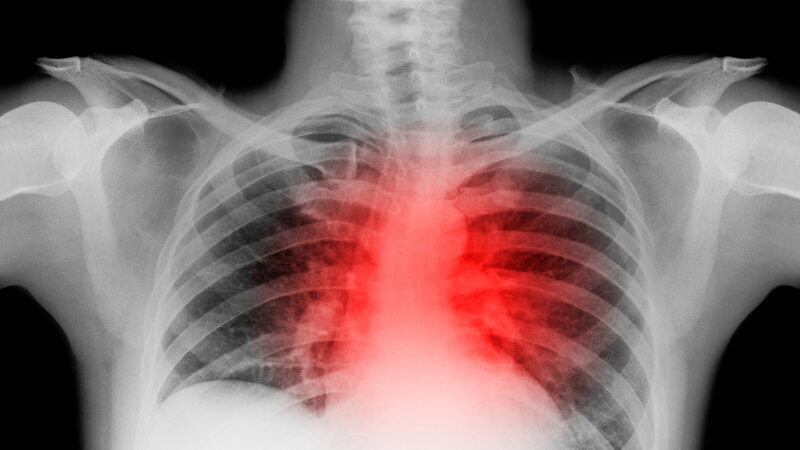

For some patients, cardiovascular problems persist long after COVID